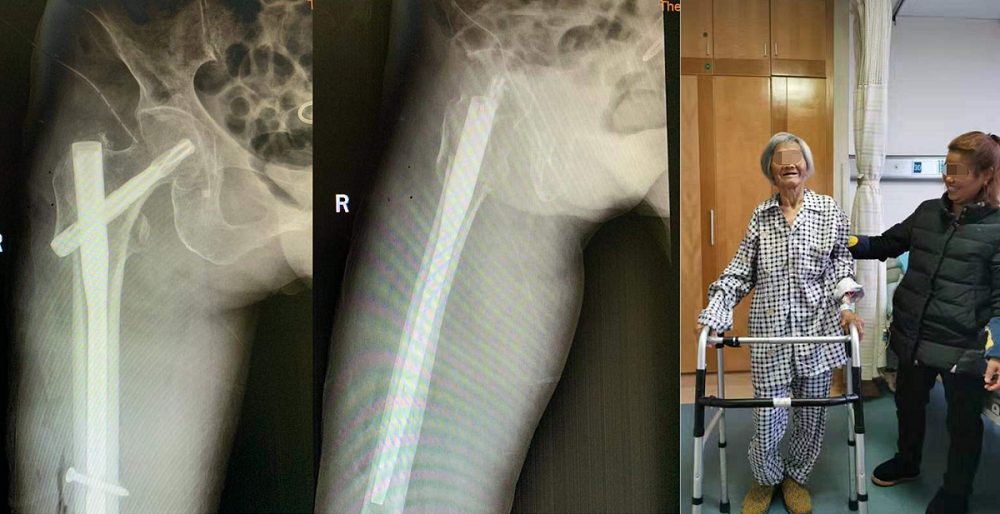

入院不到24小时,术前准备已完善。在麻醉科的协同努力下,罗令教授团队为患者行右股骨转子下骨折闭合复位+髓内钉(PFNA)固定术,手术仅用时15分钟,骨折复位且固定可靠,出血量不足50ml,手术切口不足5cm。为争分夺秒节约台上的每一分钟,医生们一直在射线下操作,当手术完成的那一刻,罗令教授脱下30斤重的铅衣,他的整个后背已被汗水浸透。微创手术、先进的“鸡尾酒”式镇痛等多模式疼痛管理,以及术后护理康复的积极介入,MDT理念渗透到了此次治疗的每一个环节。术后第二天老人便恢复了站立并缓慢行走,良好的康复获得了患者及家属的连连称赞。家属原本以为要陪老人在医院过年的忧郁也一扫而光。

近年来,中南大学湘雅三医院在党委领导下积极开展多学科诊疗模式(MDT),大大地提升了疑难重症的救治能力。作为老年髋部骨折MDT团队的重要成员,医院骨科坚决贯彻MDT核心思想,推广MDT理念,目前已成功救治多名高龄老人,并召开一次国内学术会议推广经验,为广大人民群众的生命健康保驾护航。